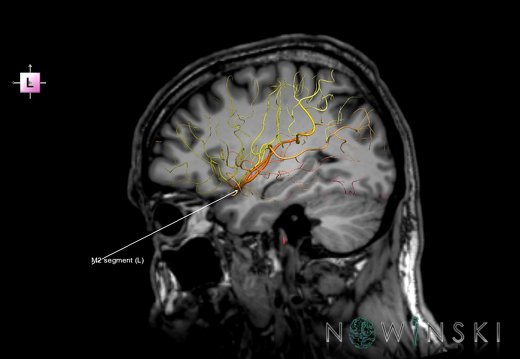

G6.T15.2.V2.P30.Intracranial arteries–Triplanar